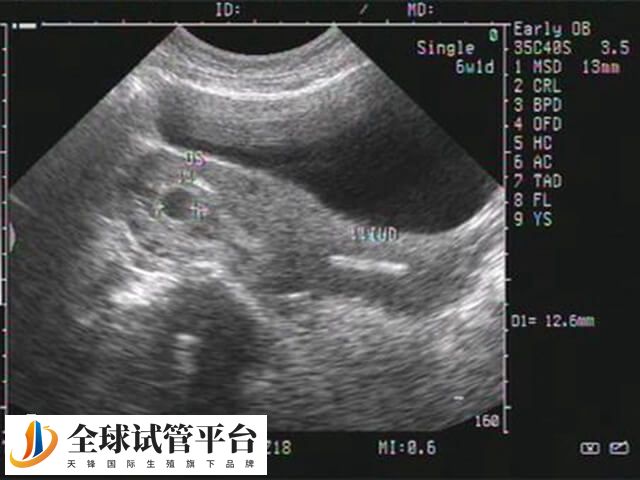

- 通常情况下,试管移植30天左右会B超看到孕囊,然后在发育至40天左右就可以观察的胎心胎芽,出现此状态表现时,表示为胚胎开始正常发育的一个重要标志;

- 一般在试管婴儿移植后42-44天左右再次进行B超检查,可以评估胚胎的同步生长情况,随后患者通过B超判断胚胎发育前,可遵医嘱进行相关检查。